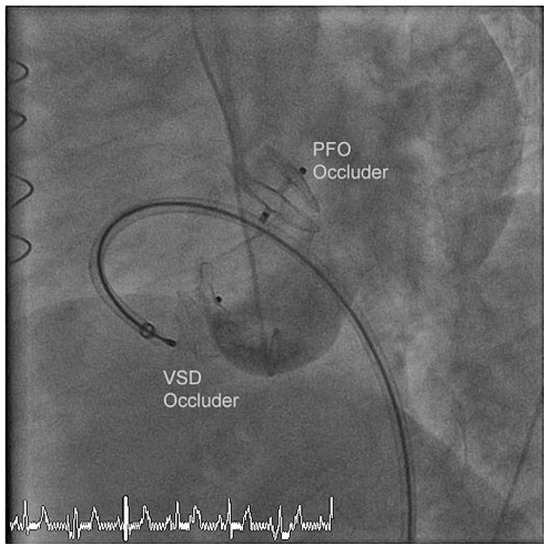

A Case for Incidental Coronary Angiography During Percutaneous Closure of the Patent Foramen Ovale?

by Nikesh Raj Shrestha, Thomas Pilgrim, Alexander Kadner and Bernhard Meier

Cardiovasc. Med. 2011, 14(10), 283; https://doi.org/10.4414/cvm.2011.01616 - 26 Oct 2011

A 42-year-old male had undergone a successful closure of a patent foramen ovale (PFO) seven years earlier for cryptogenic stroke. In spite of several risk factors an incidental coronary angiogram was not performed due to his young age (35 years at that time). [...] Read more.

A 42-year-old male had undergone a successful closure of a patent foramen ovale (PFO) seven years earlier for cryptogenic stroke. In spite of several risk factors an incidental coronary angiogram was not performed due to his young age (35 years at that time). Seven years later a myocardial infarction (MI) caused an apical ventricular septal defect (VSD) necessitating a surgical correction. Finally device closure became necessary due to patch dehiscence. Incidental coronary angiography on the occasion of PFO closure would have resulted i n timely coronary treatment by acetylsalicylic acid and a statin and perhaps coronary angioplasty. The MI and its complicated course could most likely have been prevented. Full article

Show Figures

Figure 1